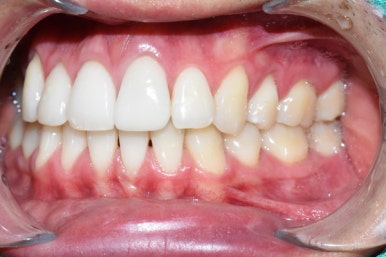

크라운 장착 후

치료전후 사진